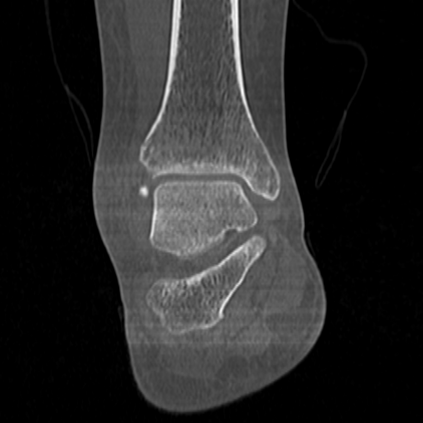

CT reconstruction provides radiologists with images for diagnosis and treatment, yet current deep learning methods are typically limited to specific anatomies and datasets, hindering generalization ability to unseen anatomies and lesions. To address this, we introduce the Multi-Organ medical image REconstruction (MORE) dataset, comprising CT scans across 9 diverse anatomies with 15 lesion types. This dataset serves two key purposes: (1) enabling robust training of deep learning models on extensive, heterogeneous data, and (2) facilitating rigorous evaluation of model generalization for CT reconstruction. We further establish a strong baseline solution that outperforms prior approaches under these challenging conditions. Our results demonstrate that: (1) a comprehensive dataset helps improve the generalization capability of models, and (2) optimization-based methods offer enhanced robustness for unseen anatomies. The MORE dataset is freely accessible under CC-BY-NC 4.0 at our project page https://more-med.github.io/